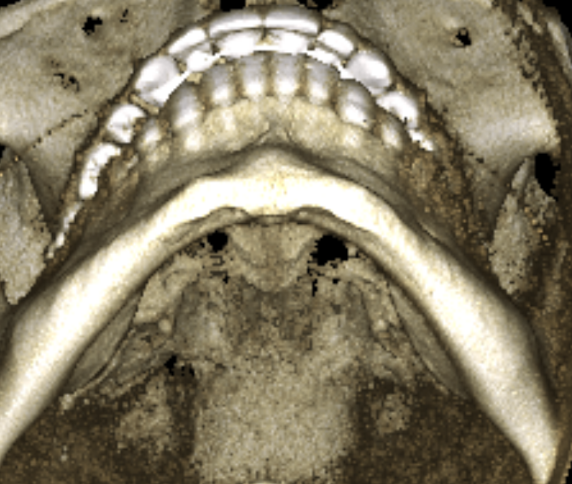

damn bro, def a bone borne appliance, probably MSE and best to choose SARPE because that cut could differentiate you getting the split or wasting money and going through the hustle again

seems to be centered, it's just the alveolar bone playing tricks with you head, your teeth are a lil overcrowded and the "midline" in the teeth has "shifted" (thankfully because of the xray you can see that with braces a clear aligner or even a toothborne expander you could fix your overcrowded lower teeth and move the "mid-line" to the right spot, your occlusion doesn't follow the "guide lines" of the bones also I notice that the upper jaw seems to be inlign with the "midline"(teeth and the base of the nasal cavity as you can see in the image)

IDK dude if I where you(and still broke) I'd do clear aligners and then a tooth expander(because I'm broke if you are not then deff SARPE)